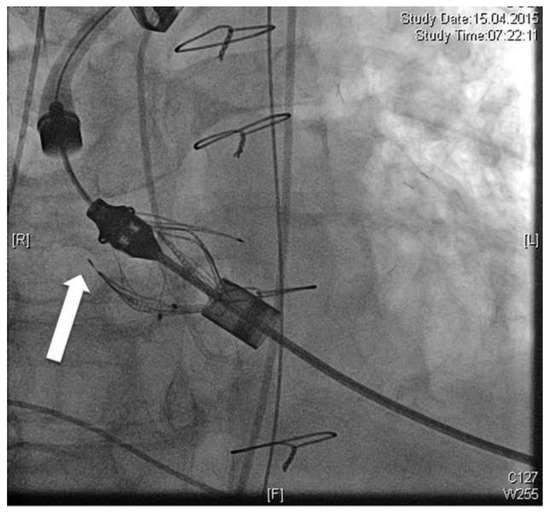

We present a case of false deployment of a self-expandable transcatheter aortic valve implantation (TAVI) prosthesis due to inadvertent and incorrect release of an eyelet in the crown of the valve resulting in a tilted valve. Hence the prosthesis had...